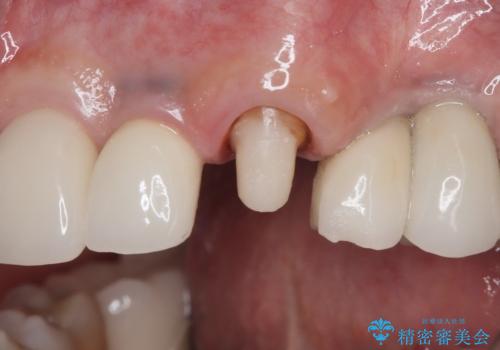

- 「被せ物が揺れている」を主訴に来院された患者様です。診査診断を行い被せ物が外れているのではなく、コアという土台ごと外れていたので、土台ごとやり変えた後オールセラミッククラウンで治療を行いました。

ファイバーコアという土台を建てるときに唾液が入ると接着に良くないのでラバーダムシートを使用しています。加えてマイクロスコープを使用しながら行う事で外れにくい土台を作ることが出来ます。その後、形成を行いシリコンで型取りしたのち、オールセラミッククラウンで修復しました。